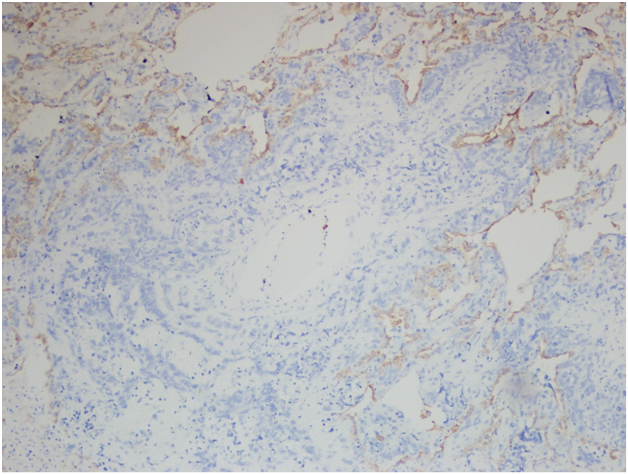

However, the wedge resection of the right lower lobe revealed angiosarcoma with lymphovascular invasion. This biopsy showed highly atypical and large malignant cells with increased mitoses (Figure 2A&2B). The immunohistochemical stains showed diffuse positivity for CD31, CD34, and vimentin (Figures 3A-3C). Stains for AE1/AE3 (Figure 3D), cam5.2, TTF-1, desmin, and OCT3/4 were negative. Along with the clinical history, a final diagnosis of angiosarcoma of the heart with metastases to the lungs was made.